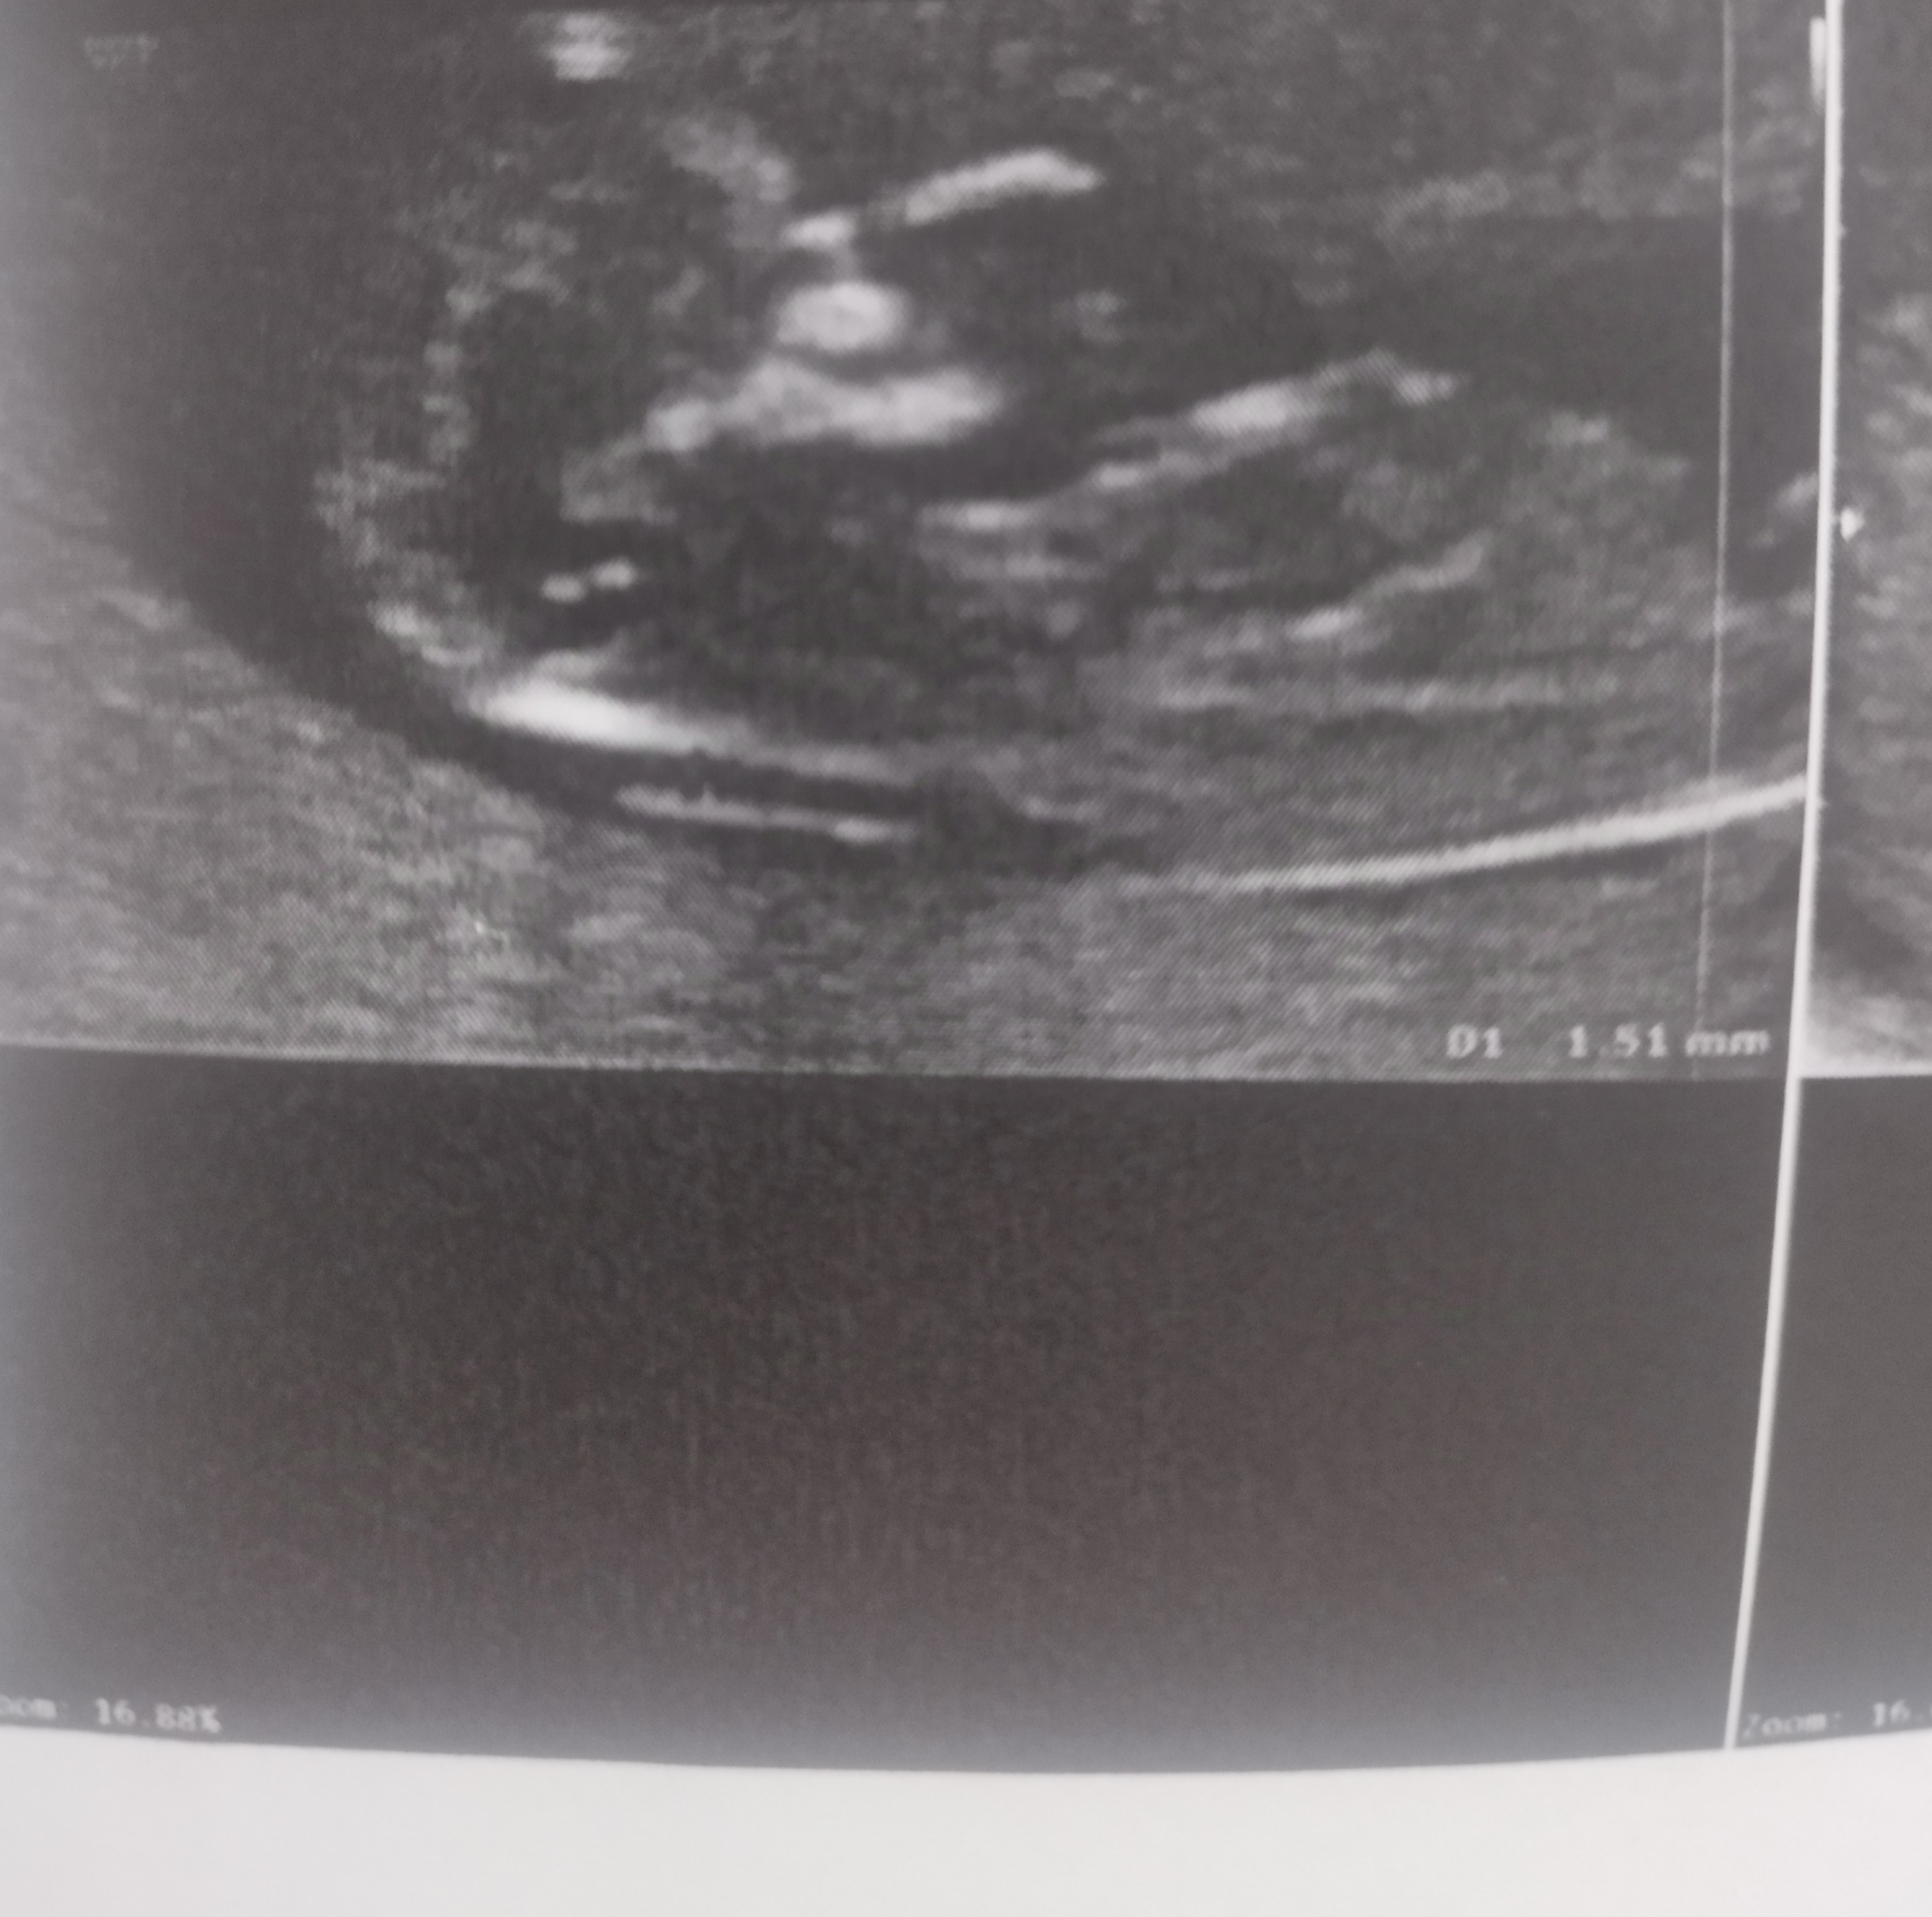

خب درصد خطا وجود داره دلیل نمیشه برا ایشون درست بوده باشه برا شمام درست دربیاد یکی از فامیلای ما تا ۷ ماهگی گفته بودن پسره یهو دختر از آب دراومد حالا چیزی نمیشه که به کسی چ مربوط بچت دختره یا پسر تغییر هم کنه میگی سونوگرافی تشخیص اشتباه داده بود اینکه نگرانی نداره

چیزی نمی گن برای من زشت می شه با 70%خطا داره الان شما به سونو نگاه می کنید دختر یا پسر